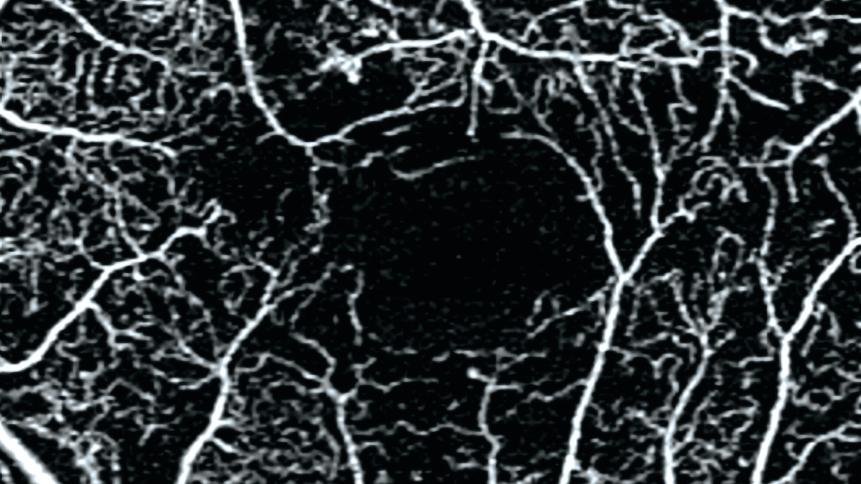

• 6x6 mm HD AngioPlex OCTA of non-proliferative diabetic retinopathy (NPDR)

6x6 mm HD AngioPlex OCTA of non-proliferative diabetic retinopathy (NPDR).

Image courtesy of Roger Goldberg, MD, Bay Area Retina Associates, United States